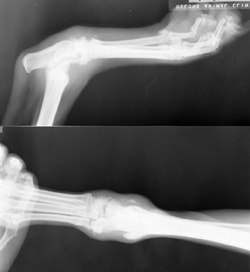

Hands In the Primary Beam